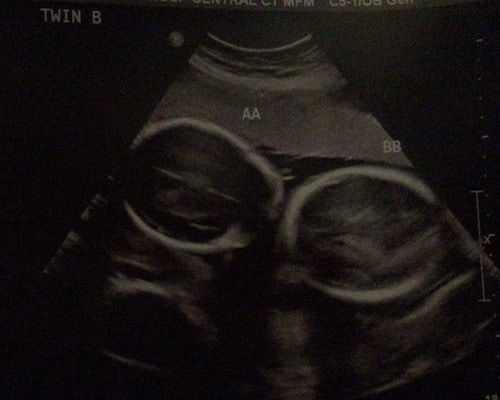

Ultrasound Photos at 25 Weeks Pregnant With Twins